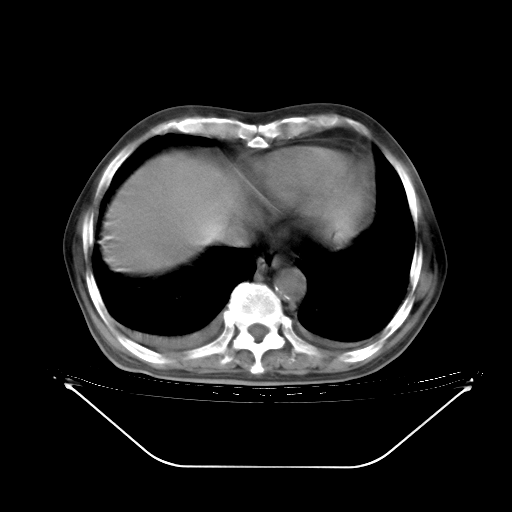

今天复查肺部CT,发现双肺广泛磨玻璃样改变。所以我把3月19日和5月9日相隔50天的肺部CT上传。请大家会诊。

5月9日肺部CT(在4月27日齐鲁医院肺部CT描述部分肺组织磨玻璃样改变,12天后肺组织广泛磨玻璃样改变)

2009年5月9日肺部CT

大致读了系列胸部CT:纵隔窗无明显异常,肺窗:从4、27至今:主要是双肺中下野外带可见毛玻璃样改变,目前处于急性肺泡炎阶段,至于原因考虑1、结替组织或胶原血管性疾病所致?2、恶性疾病如恶组在肺部所致的表现或细支气管肺泡癌?3、药物或其它原因如肺蛋白沉着症所致肺泡炎目前不太可能?总之,明天就去请我院的呼吸科、感染科、血液科和临免专家会诊哈。